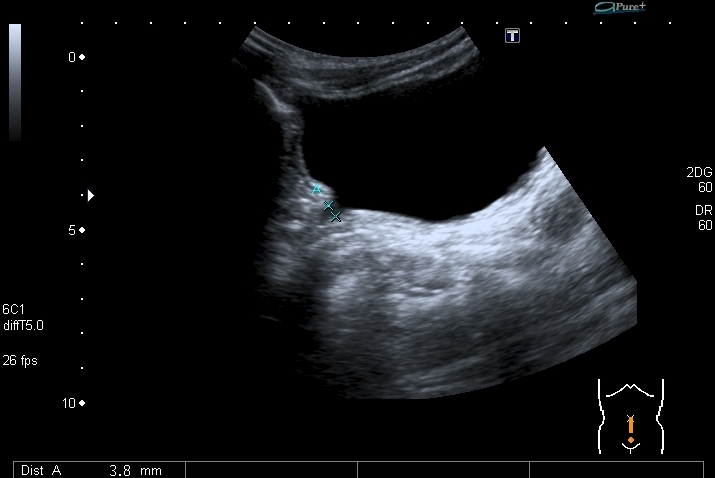

Почки:

Определяется небольшое расширение лоханок обеих почек, стенки их гиперэхогенные, утолщены.

Меня больше всего заинтересовало тканевое образование в нижнем полюсе левой почки - гиперэхогенное, многоузловое. Есть мысли про причину такого состояния почек, но пока хочу выслушать мнения коллег. Буду очень благодарен за отзывы.

Спленомегалии нет. печень без признаков фиброза . Почки уменьшены ( правая - 50 х 20 мм, левая - чуть больше , но за счёт образования нижнего полюса). В левой почке в образовании - есть одиночная небольшая киста ( см клип про почки №3), но на поликистоз непохоже. Ещё одно "но" : с аутосомно - рецессивной поликистозной болезнью почек до 10 лет не живут.